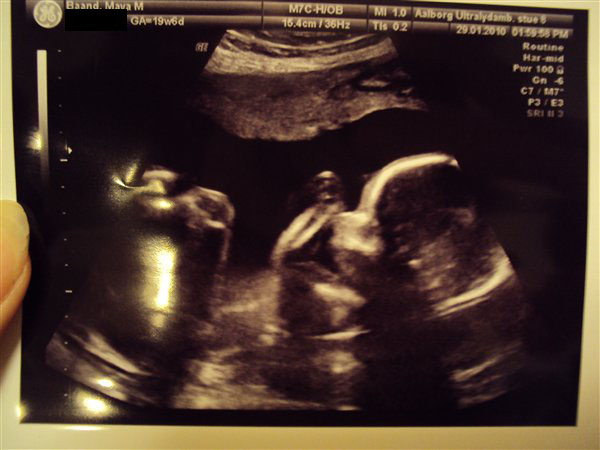

Her kommer så det bedste billede jeg kunne tage med mit kamera. Her kan man også se arme og lår.

Håber det er godt nok, selv om det er med et kamera